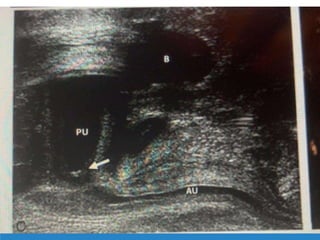

IN UTERO

1ST STEP-( U.S.G.)

Evaluated bladder before and after fine needle vesicocentesis.

Rule out other anamalies like NTD,CVS.

Kidney condition(large hyperechogenic or small hyperechogenic).

Needle Aspiration of Bladder

2ND STEP:-

Prenatal evaluation for fetal karyotype.

Amniocentesis if fluid available.

FINAL STEP:-

Evaluation of fetal kidney function with sequential vesicocenteses

Completely drain fetal bladder at 48-72 hr intervals at a minimum of

three occasions.

progressive hypotonicity and values that fall below threshold benefit

from in utero intervention i.e. shunt placement.